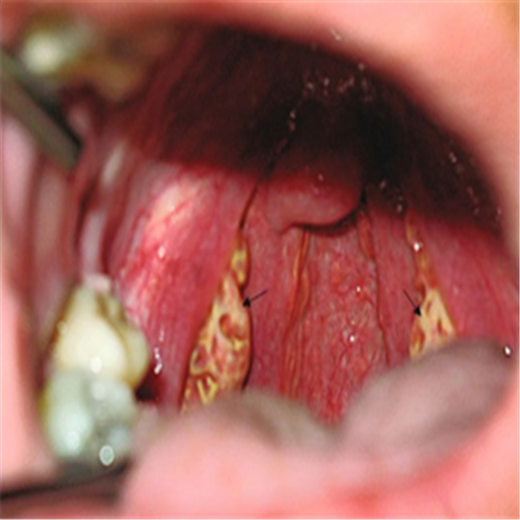

扁桃體炎圖片

扁桃體腫大